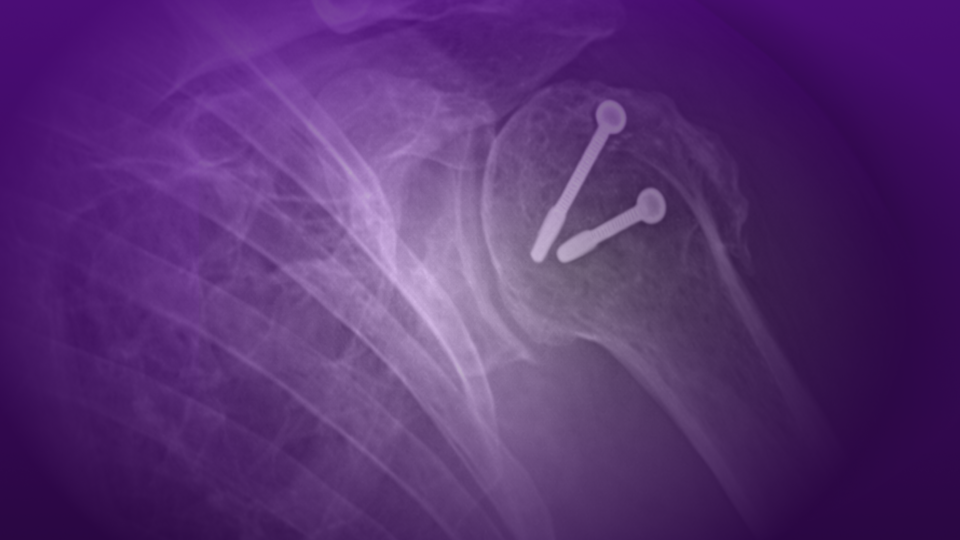

The specialized procedure restored right thumb function via osseointegration surgery with osseoperception.